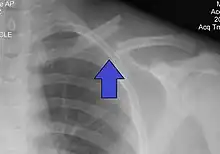

X-ray of a left clavicle fracture

It is often caused by a fall onto a shoulder, outstretched arm, or direct trauma.[1][3] The fracture can also occur in a baby during childbirth.[1] The middle section of the clavicle is most often involved.[3] Diagnosis is typically based on symptoms and confirmed with X-rays.[2]

The basic method to check for a clavicle fracture is by an X-ray of the clavicle to determine the fracture type and extent of injury. In former times, X-rays were taken of both clavicle bones for comparison purposes. Due to the curved shape in a tilted plane X-rays are typically oriented with ~15° upwards facing tilt from the front. In more severe cases, a computerized tomography (CT) or magnetic resonance imaging (MRI) scan is taken. However, the standard method of diagnosis through ultrasound imaging performed in the emergency room may be equally accurate in children.[5]